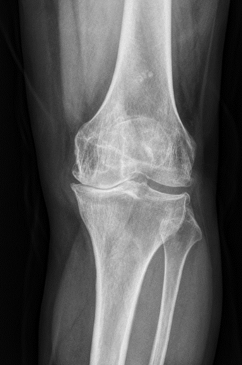

术前关节内翻畸形